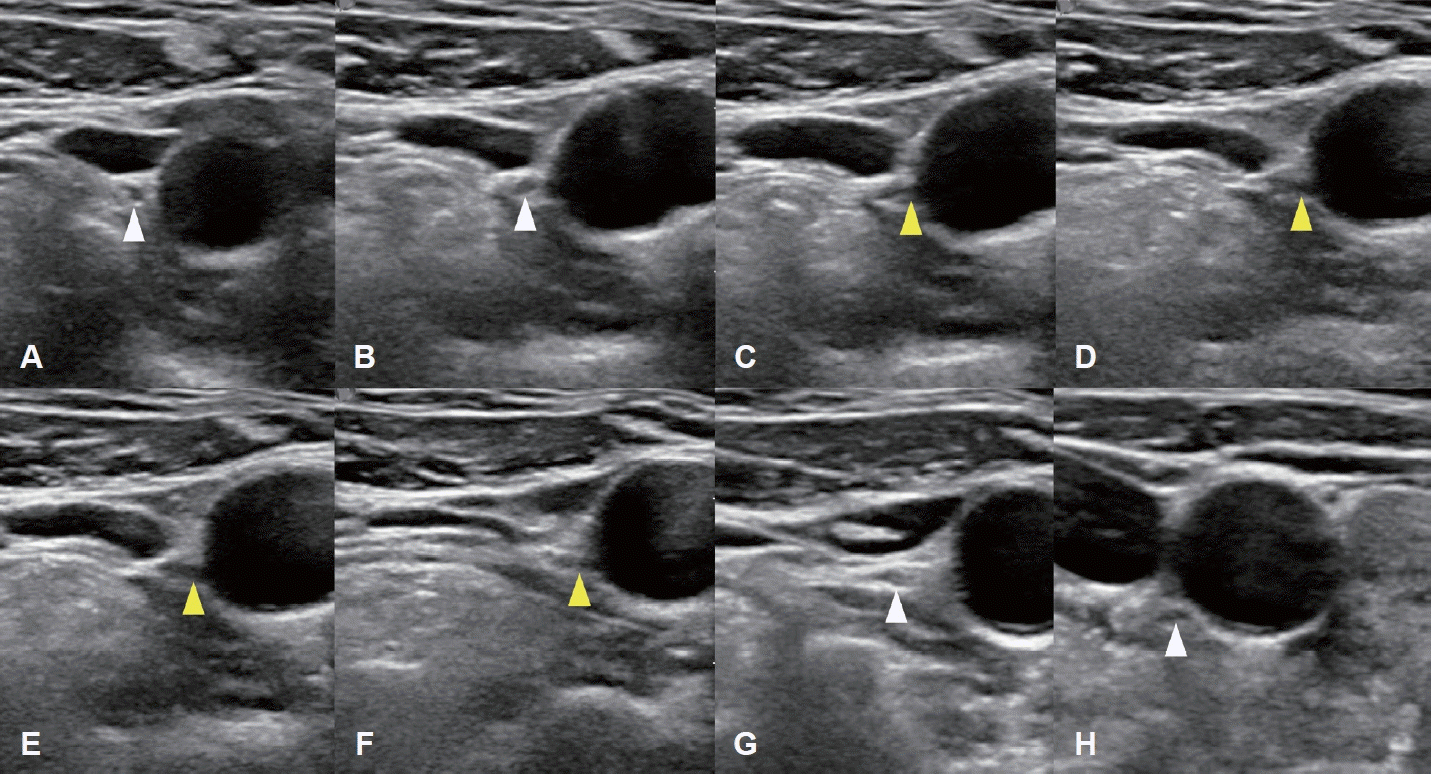

78세 여성이 한 달 전부터 발견된 전방 경부 종괴를 주소로 내원하였다. 신체검사 및 촉진 결과 갑상선 종괴가 의심되었고, 수일 후 시행한 초음파 검사에서 좌측 협부에 44 mm 크기의 갑상선 결절이 확인되어 중심바늘생검(core needle biopsy)을 시행하였으며, 갑상선 유두암(papillary thyroid cancer)이 진단되었고 초음파와 조영증강 갑상선 CT (thyroid CT)를 시행하였으며 수술 전 임상병기는 cT3bN0으로 판정되었다. 경부 초음파 검사는 고해상도 초음파 기기(EPIQ7, Philips Healthcare)와 5-12 MHz 선형탐촉자를 사용하여 갑상선 및 두경부 초음파에 숙련된 영상의학과 전문의에 의해서 수행되었다. 조영증강 갑상선 CT는 갑상선암 진단에 최적화된 대한갑상선영상의학회에서 제시한 표준검사기법으로 수행되었으며[1], 조영제 주입 후 35초 시점에 영상이 획득되었고, 2 mm 절편 두께로 횡단면, 관상면, 시상면 영상이 재구성되었다. 갑상선 전절제술 및 중앙 경부절제술을 계획하였고 thyroid CT에서 우측 이상 쇄골하동맥이 확인(Fig. 1)되어 비반회후두신경 가능성을 고려하여 비반회후두신경 평가를 위해 수술 전 경부 초음파를 추가로 시행하였다. 비반회후두신경의 초음파 평가는 설골 부위에서부터 미주신경을 초음파로 확인한 후에 미주신경을 하방으로 연속적으로 추적하여 미주신경에서 내측으로 분지되는 신경 유무를 평가하였다. 본 증례에서는 초음파 검사에서 갑상연골 높이의 미주신경으로부터 직접 분지되어 총경동맥 후방 쪽으로 주행하는 저에코의 신경 가지를 확인하였다(Fig. 2). 이후 예정된 수술을 시행하였으며, 피부 절개 후 갑상선 검체를 박리하는 과정에서, 한국 표준화된 신경모니터링 방법2)을 사용하여 수술 중 신경모니터링을 적용하였고, 모니터는 잘 작동하였다. 수술 시 type II 비반회후두신경을 확인하였으며(Fig. 3), 수술 중 신호손실(loss of signal) 등의 문제는 없었으며, 수술 직후 및 외래 추시 시 내시경 검사에서 성대마비는 관찰되지 않았으며(Fig. 4), 입원 중 특이 합병증이 관찰되지 않았다. 병리 결과는 유두암, 고전형(classical type), 단일 결절(3.9×3.0×3.0 cm), 갑상선 외 침범(macroscopic extrathyroidal extension) 및 좌측 6번 경부 구획에서 한 개 림프절에서 미세 림프절 전이가 확인되었다. 림프혈관 침윤, 신경 침윤, 외측 절제면 침범은 없었다. 환자는 내분비내과에서 정기적인 추적 검사를 진행하며, 방사선 요오드 치료(radioactive iodine)를 권고하였으나 환자의 의사에 따라 시행되지 않았다. 내분비내과에서는 권장했지만, 환자는 이를 거부하였다. 추적 검사에서는 T3, T4, 갑상선자극호르몬, 갑상선글로불린 등을 포함한 갑상선기능 검사 및 화학검사에서 정상 범위 수치를 보였다.

Serial ultrasonographic tracking images of the NRLN obtained using a 5–12 MHz linear-array transducer. A-F: A series of transverse ultrasound images arranged in craniocaudal order shows the suspected right NRLN (yellow arrowheads). A and B: The right vagus nerve (white arrowheads) is visualized between the IJV and CCA at the level of thyroid cartilage. C and D: A nerve branch is seen arising directly from the right vagus nerve. E and F: The nerve branch courses horizontally and medially toward the CCA. G and H: The descending vagus nerve (white arrowheads), separated from the NRLN, is seen at the level of the cricoid cartilage and thyroid gland. This direct, non-recurrent path from the right vagus nerve at the level of the larynx is highly suggestive of an NRLN. NRLN, non-recurrent laryngeal nerve; IJV, internal jugular vein; CCA, common carotid artery.